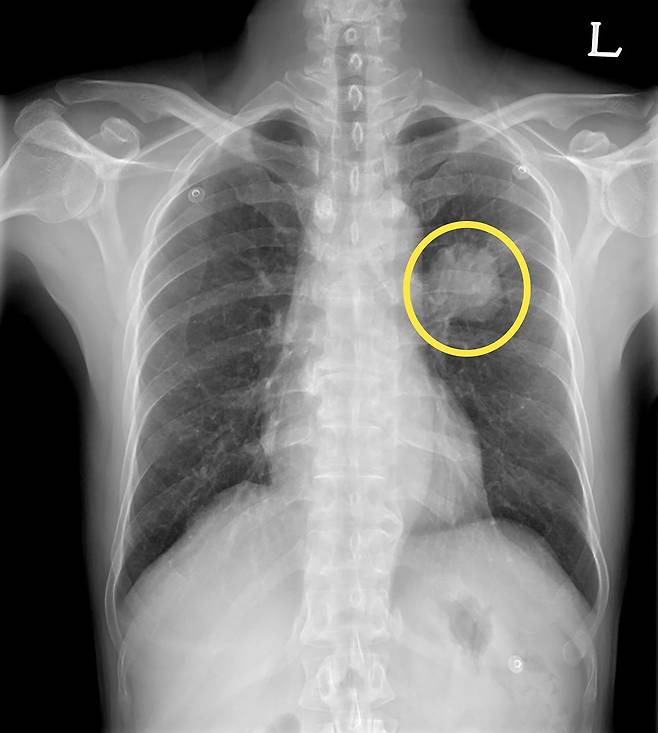

56세 여성 이모 씨는 평소 담배를 피운 적이 없고 기침, 흉통과 같은 호흡기 증상도 없었다. 어느 날 소화가 잘 되지 않고, 상복부 불편감이 지속돼 병원을 찾아 복부 CT 검사를 받았다.

검사 결과 위나 간에 큰 이상이 없었지만 영상 판독 과정에서 폐 하부에 작은 결절이 우연히 발견됐다. 의료진은 추가로 흉부 CT 검사를 시행했고, 정밀 검사 결과 초기 폐암이 의심돼 수술을 진행했다. 다행히 암이 초기 단계에서 발견돼 최소 침습 수술만으로 제거할 수 있었고 현재는 항암치료 없이 정기 추적 관찰을 받고 있다.